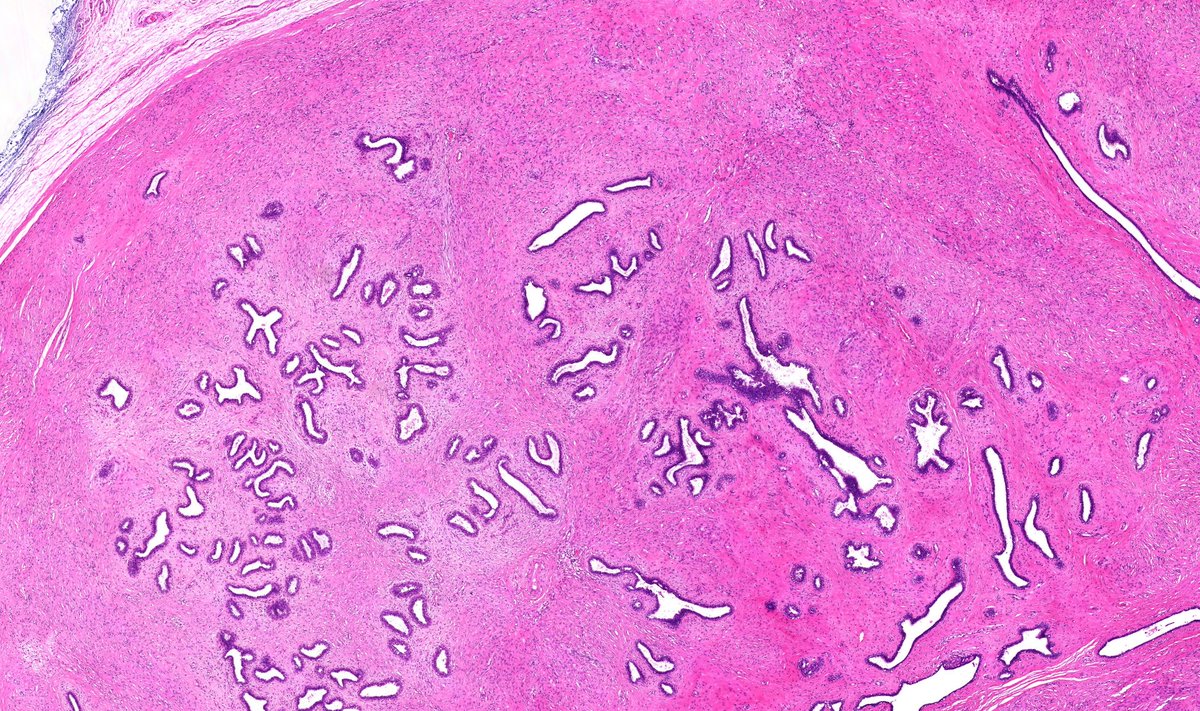

@JenyaMD

Jennifer Moreira-Dinzey

1 year

Papillary RCC showing type 1 and type 2 morphologies. #GUpath #pathology